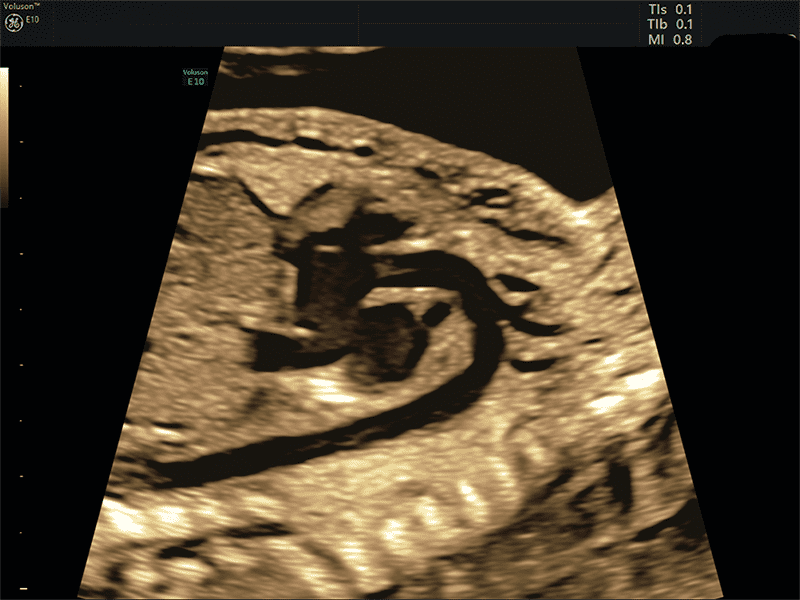

Slowflow 3D: È possibile abbinare le varie tecnologie Volume Ultrasound integrate nella piattaforma per uno studio approfondito delle strutture vascolari del cervello fetale, dei vasi addominali e in applicazioni ginecologiche, quali lo studio dell’adenomiosi tramite Slowflow 3D.

SlowflowHD™: software per lo studio della vascolarizzazione che grazie all’altissima sensibilità è in grado di sopprimere i movimenti a bassa frequenza preservando le informazioni sul flusso.